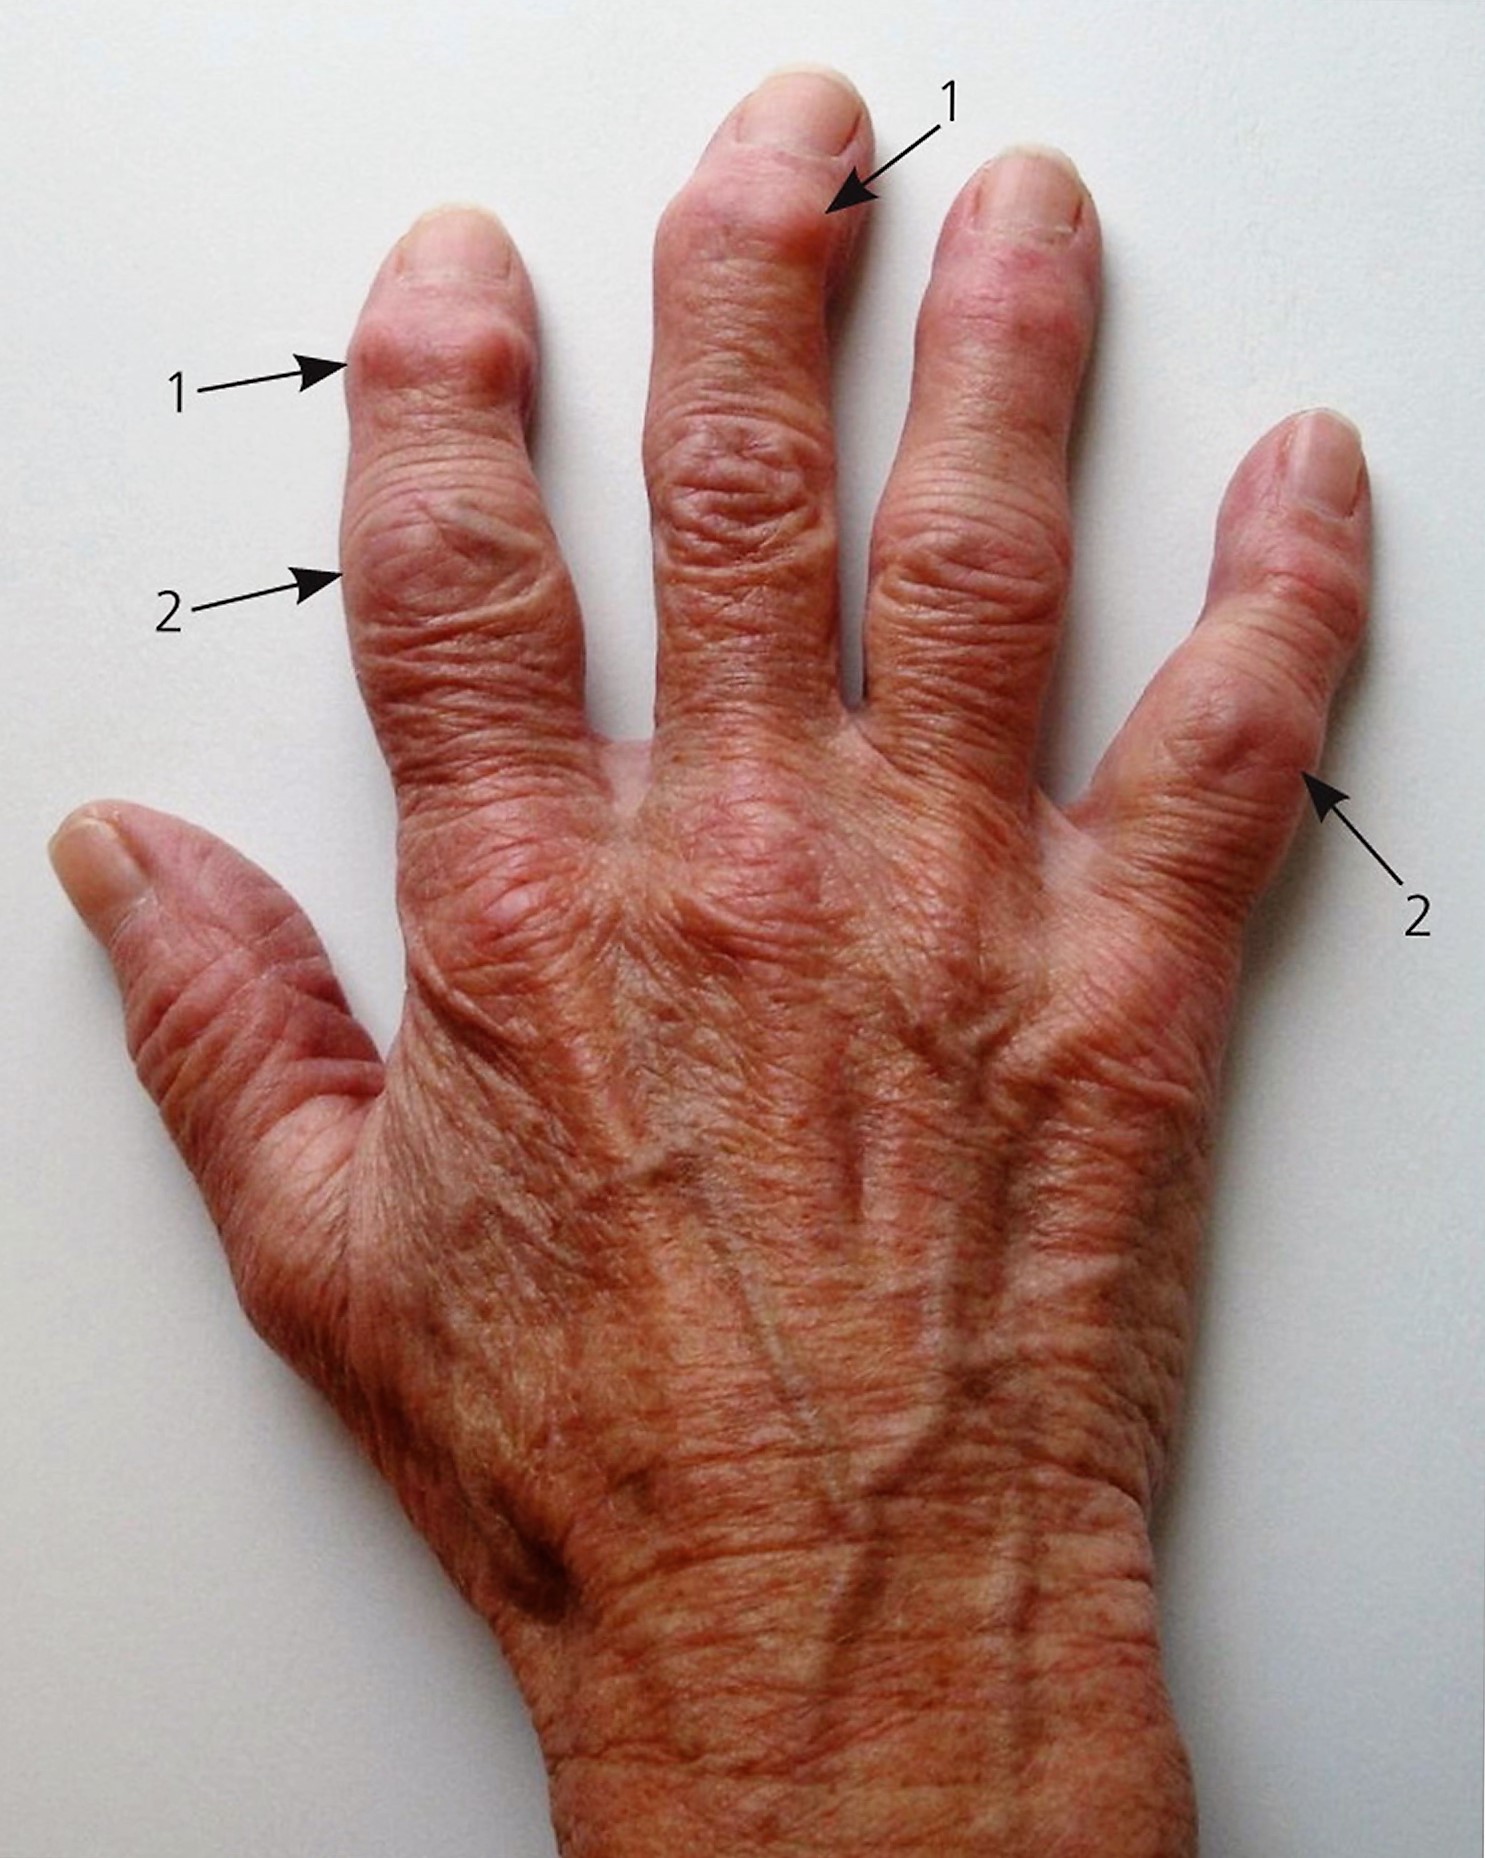

Arthritis Pictures

Heberdenovy Uzly WikiSkripta

Finger Nodes

Rheumatic Pain Gemini Osteopathy

Heberden Nodes

Heberden Nodes

Osteoarthritis Hand

Osteoarthritis Of The Hand Stock Image C010 3320 Science Photo